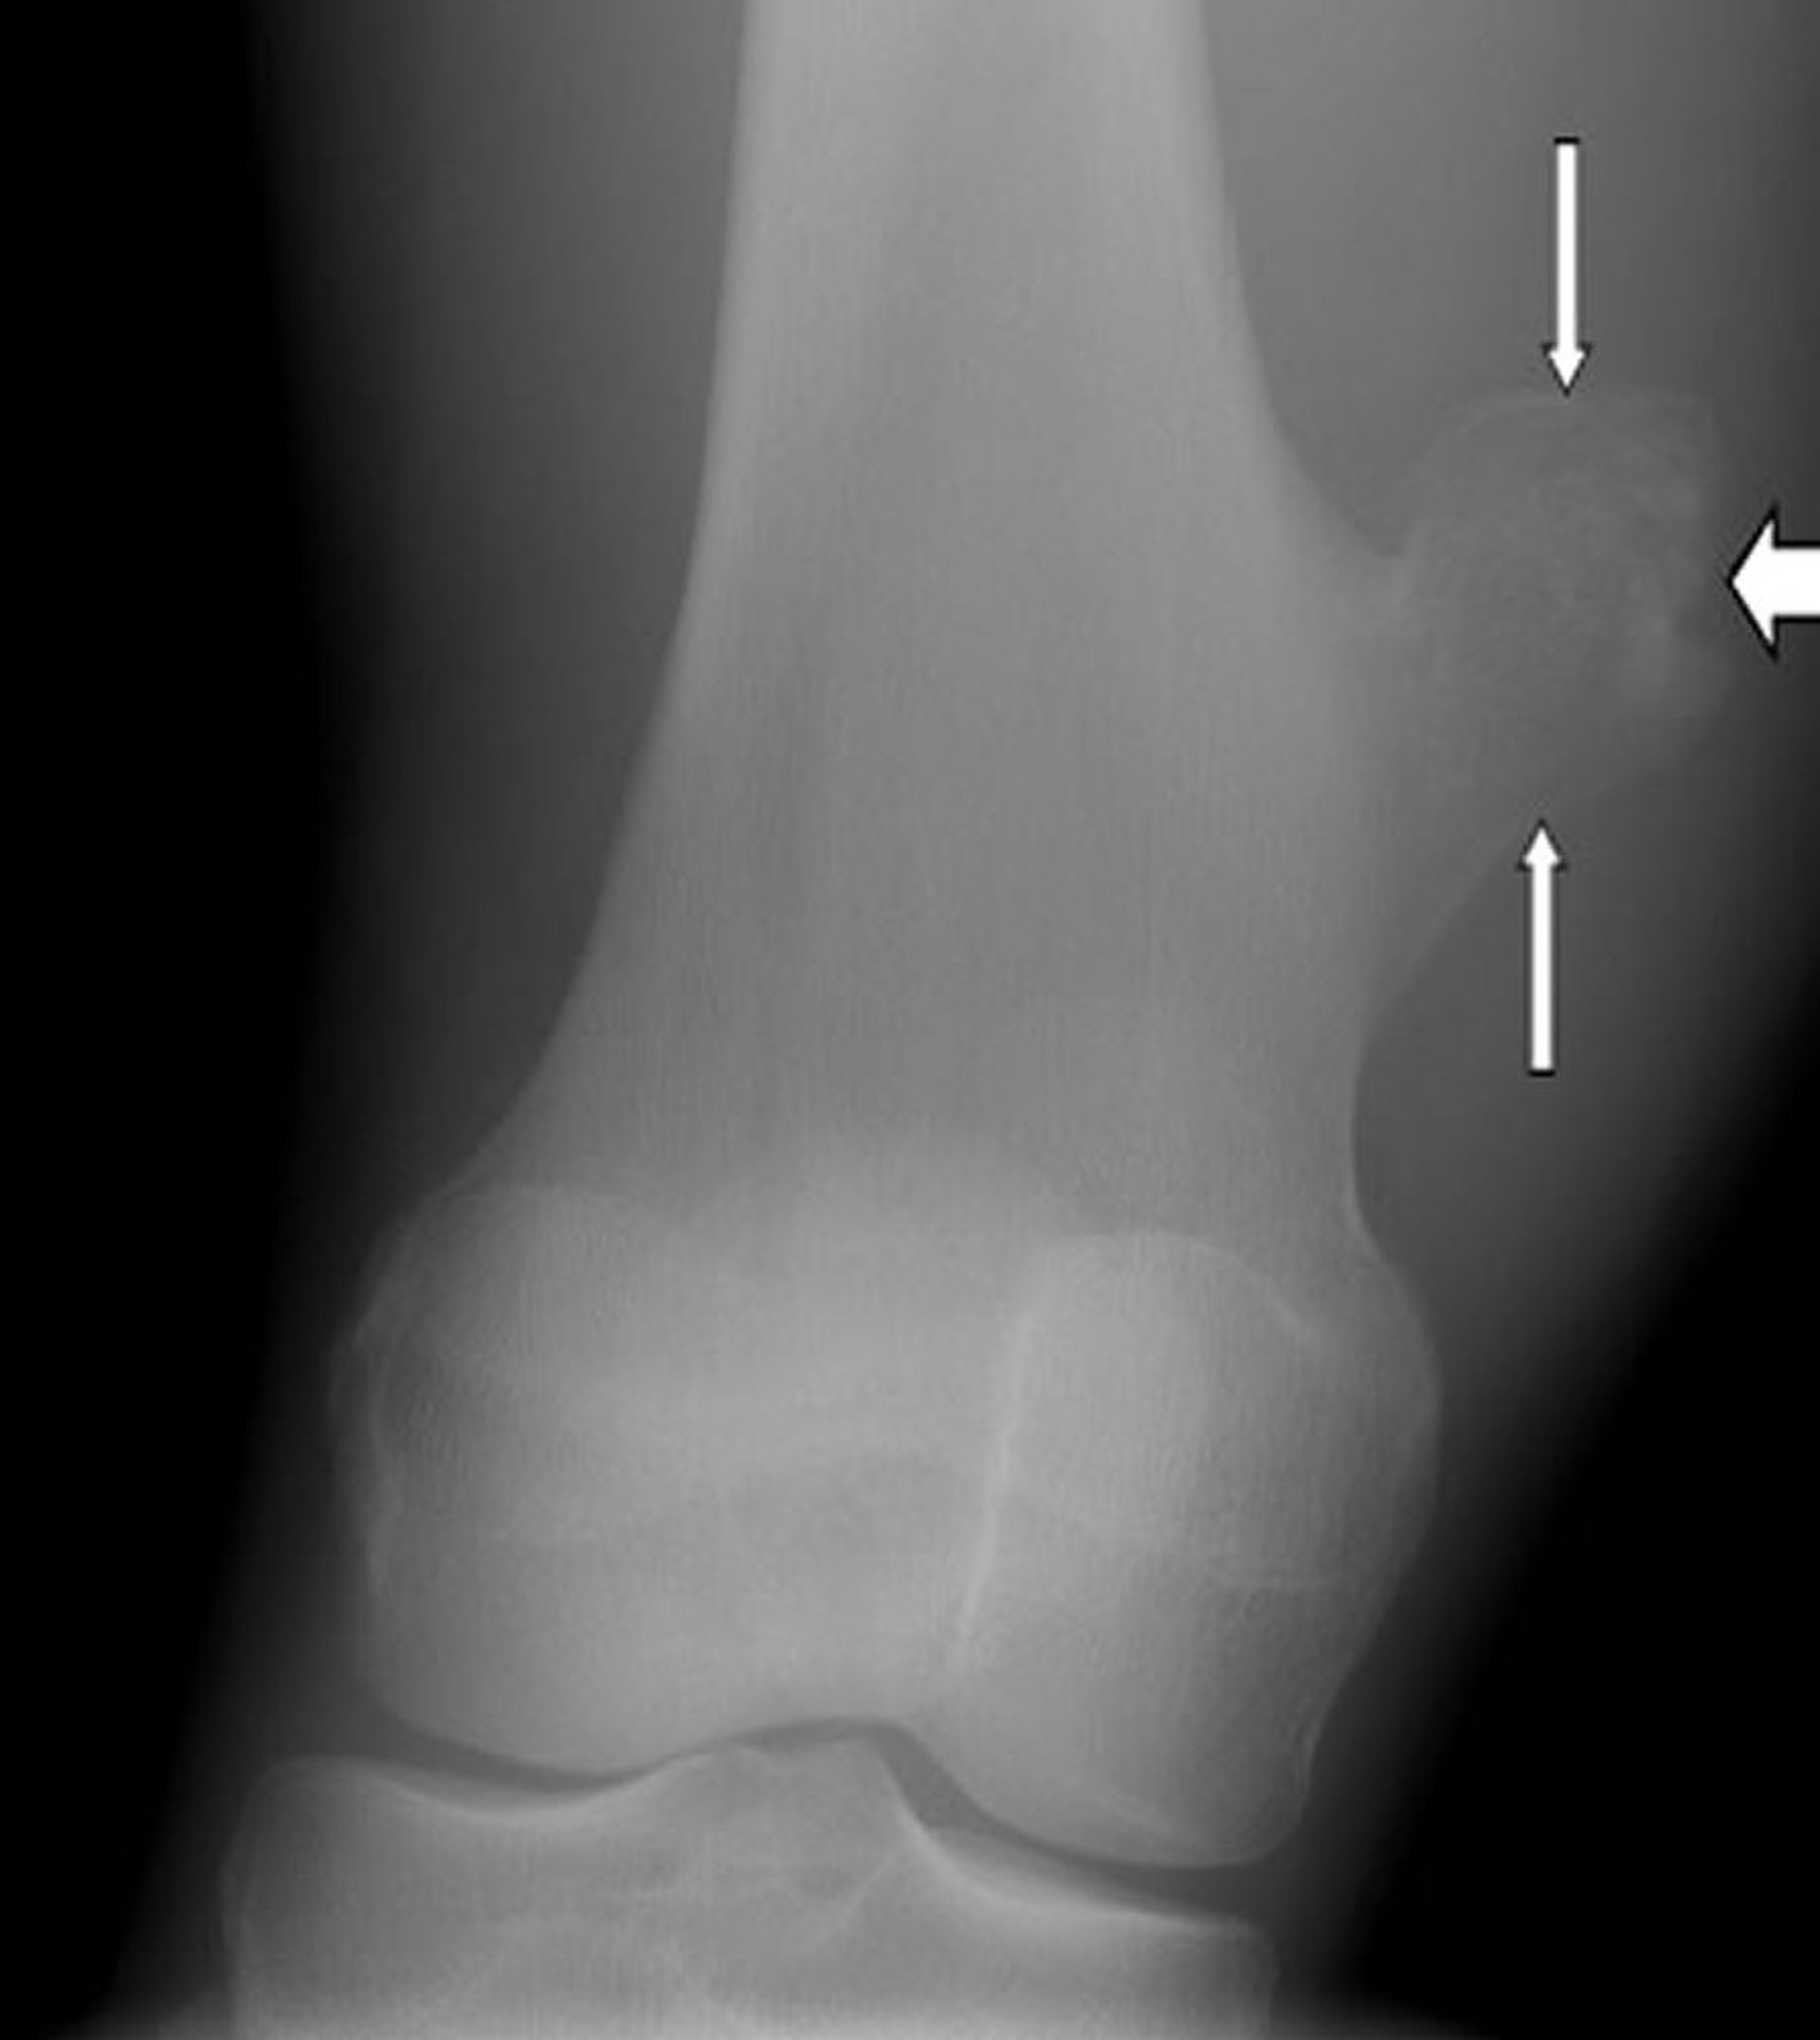

Osteocondroma de la rodilla

Esta radiografía de la rodilla muestra un osteocondroma, que es el crecimiento en la superficie del fémur (flechas) por encima de la articulación de la rodilla.

Imagen cortesía de Michael J. Joyce, MD, y Hakan Ilaslan, MD.